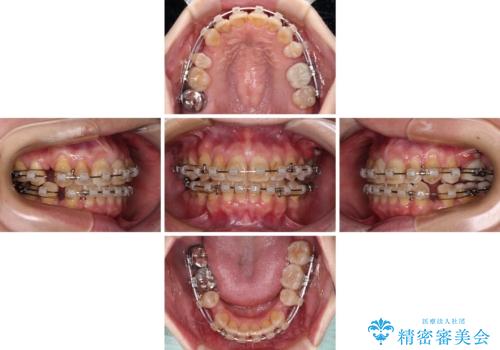

- 矯正装置

- クリアブラケット

- 治療計画

- 口元の突出感を気にして来院された患者様です。

上下前歯が著しく前突している状態であったので、上下左右の小臼歯4本を抜歯し、ワイヤー装置にて矯正治療を行うこととしました。

上顎左側は第二小臼歯に大きなむし歯があったため、通常は第一小臼歯を抜歯するところ、イレギュラーに第二小臼歯を抜歯することとしました。

抜歯する第二小臼歯の後方の歯は神経近くにまで及ぶむし歯があったため、事前に処置をしておき、矯正治療後にオールセラミッククラウンにて補綴治療を行うこととしました。

第二小臼歯抜歯はイレギュラーな治療となるため、アンカースクリューを補助的に使用して、スムーズに治療を行えるように工夫をしました。